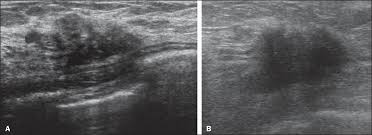

Figure 2 From Sonographic Features Of Inflammatory Breast Cancer Semantic Scholar

Figure 2 From Sonographic Features Of Inflammatory Breast Cancer Semantic Scholar from d3i71xaburhd42.cloudfront.net

It's called inflammatory because that's how it looks. Any area that does not look like normal tissue is a possible cause for concern. Inflammatory breast cancer, also known as carcinomatous mastitis, t4d, or pev 2 or 3, is the only real therapeutic emergency in breast oncology, given the high risk of metastasis, the reason for the most unfavourable prognosis of all breast cancers.it must consequently be diagnosed rapidly, and imaging examinations must in no case delay therapeutic management. Because ibc grows quickly, it is usually found at a locally advanced stage, meaning that cancer cells have spread into nearby breast tissue or lymph nodes. A breast ultrasound is a scan that uses penetrating sound waves that do not affect or damage the tissue and cannot be heard by humans. Ultrasound is useful for looking at some breast changes, such as lumps (especially those that can be felt but not seen on a mammogram) or changes in women with dense breast tissue. As these inflammatory breast cancer picture shows, the texture of the breast may change and appear to look dimpled or ridged, like an orange peel. Their differences, however, lie in their enhancement.

However, inflammatory breast cancers are more likely to show solid mass lesions. The problem is that inflammatory breast cancer can look very much like mastitis early on, and is often diagnosed only after a woman has been treated first for mastitis (often with no improvement in symptoms). This condition usually does not develop a lump, but commonly affects the breast skin. The aim of this study was to evaluate the features of inflammatory breast carcinoma (ibc) on mri compared with mammography and ultrasound and to better define the role of mri in patients with this aggressive disease. These tubes, which are hollow, allow lymph fluid to drain out of the breast.